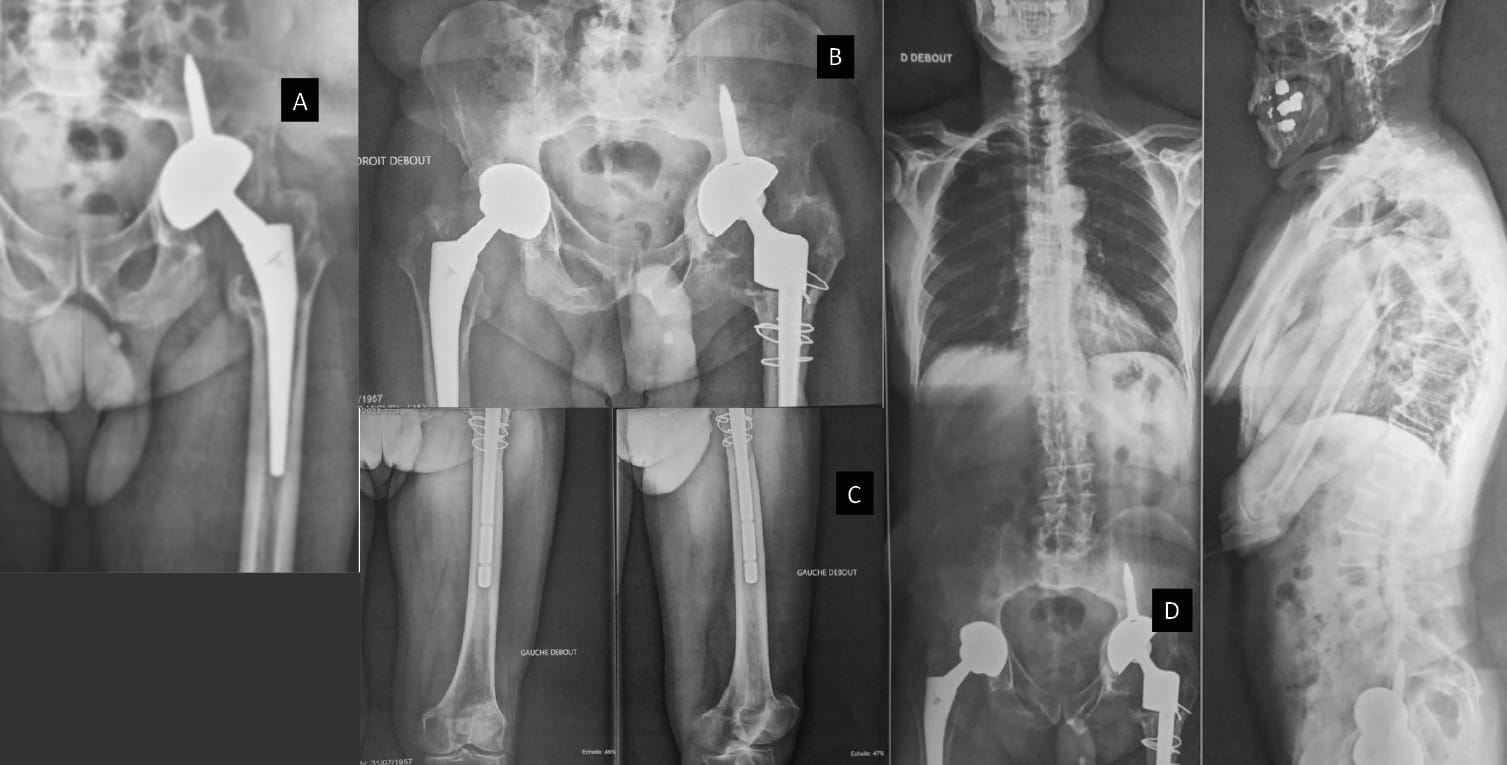

Monoblock DM with iliac stem: The ice-cream cone prosthesis

In some complex cases of revision, especially when there is structural bone loss and/or pelvic discontinuity in elderly patients, the “ice-cream cone” prosthesis can prove to be useful.

Puget et al. [47] Tricoire J-L, Puget J, Connes H, Canevet G, Moscovici J, Guittard J. Etude anatomique de l’isthme iliaque, base de fixation cotyloïdienne dans les grandes pertes de substance segmentaires lors des reprises de PTH. Morphologie 2004;88:80. https://doi.org/10.1016/S1286-0115(04)98044-7. described the iliac isthmus as an anatomical beam made up of a dense bridge with a potential entry point at the superior-medial and posterior part of the acetabulum. Fixed with a peg (as used with the Integra cup: length 5 cm, diameter 11mm and orientation 55°) inserted into the ilium [48] Desbonnet P, Connes H, Escare P, Tricoire JL, Trouillas J. Total hip revision using a cup design with a peg to treat severe pelvic bone defects. Orthop Traumatol Surg Res 2012;98:346–51. https://doi.org/10.1016/j.otsr.2012.01.006., this implant results in primary stability that allows patients to quickly regain their independence with weight-bearing from the outset. There are various models, both modular and monoblock, on the market today 49. (Figure 5). They can be used in mechanical reconstructions, in cases when a biological reconstruction using bone grafts no longer appears to be suitable.